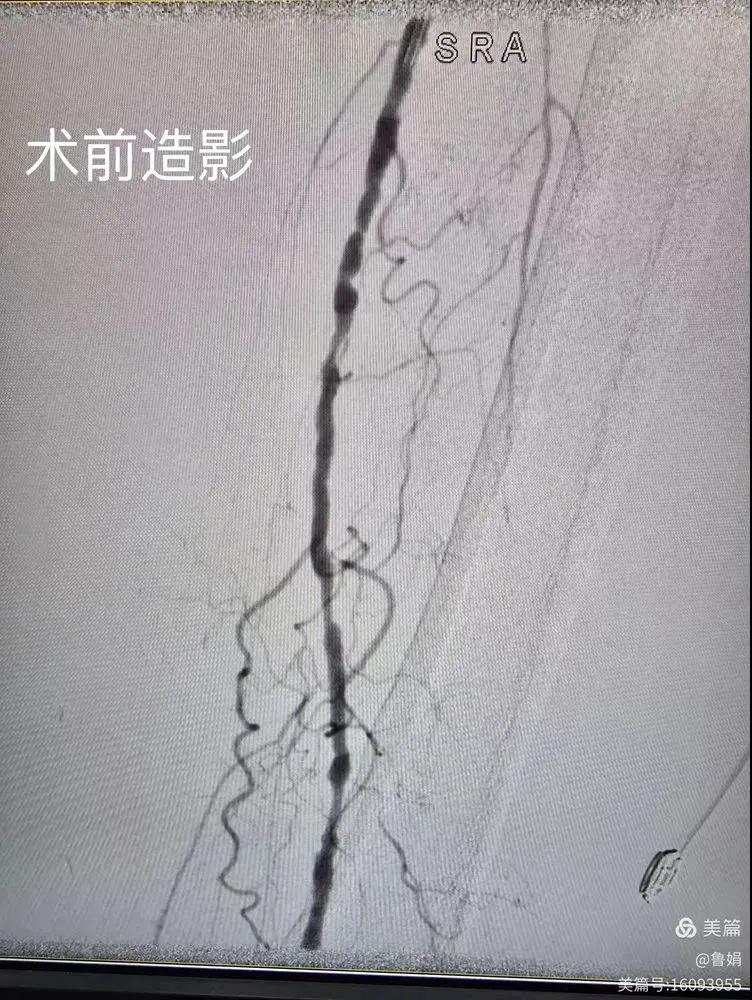

據(jù)悉,該患者,女,73歲,下肢動脈硬化閉塞癥,“以靜息痛,間歇性跛行”入院,CTA評估:股淺動脈,腘動脈間斷性多段重度狹窄,外二科血管外科團(tuán)隊(duì)根據(jù)患者病情,結(jié)合檢查結(jié)果,經(jīng)過科室會診后,決定對該病人行介入治療。手術(shù)由周創(chuàng)業(yè)副主任與北大一院血管外科專家郭宏杰教授聯(lián)合開展,對股淺動脈,腘動脈重度閉塞段行血管開通+藥涂球囊擴(kuò)張成形,術(shù)后狹窄明顯緩解,血流恢復(fù)!